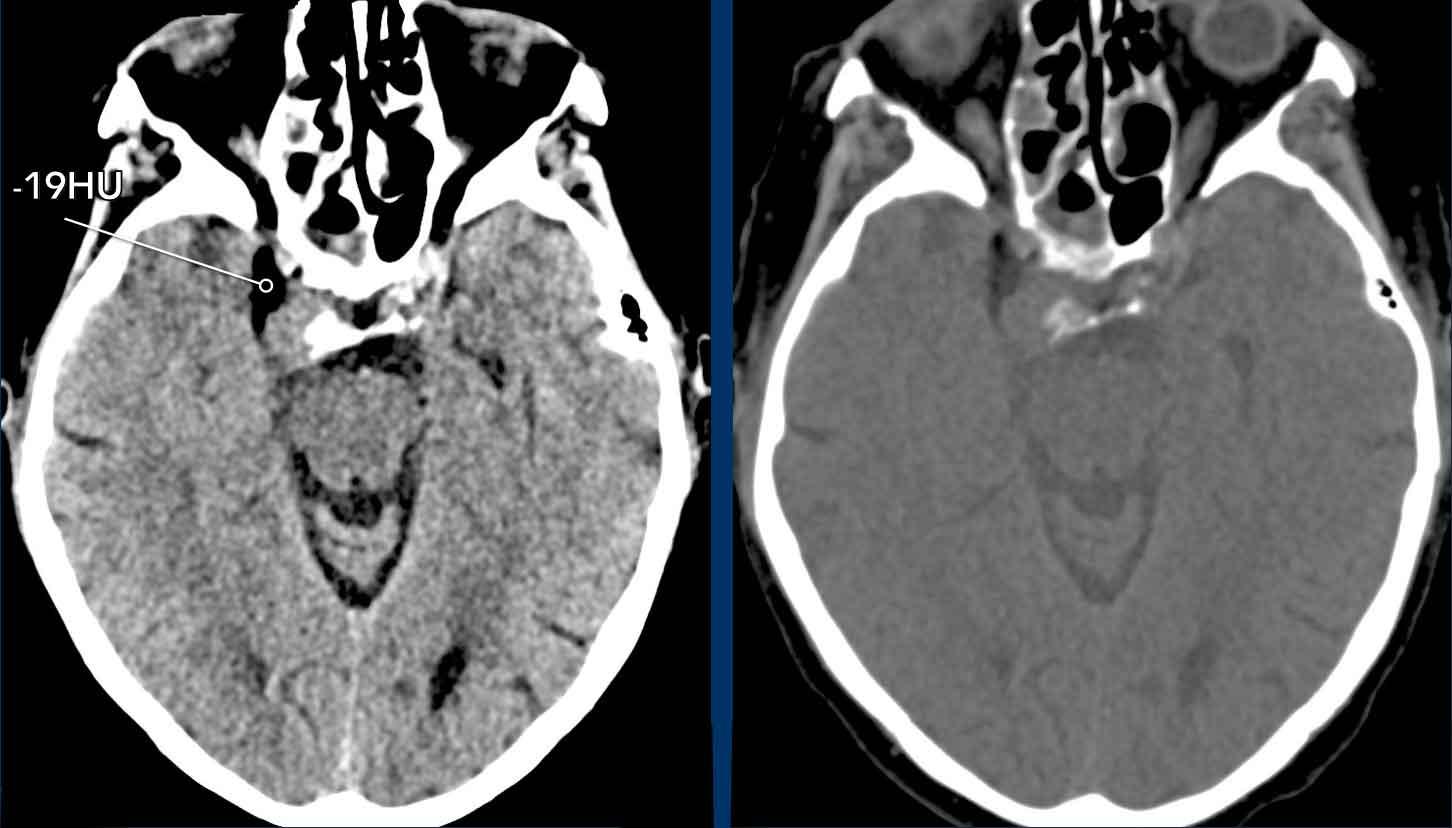

Case 5

This

is a similar case.

Hình ảnh

Lưu ý

trên CT không tiêm thuốc cản quang bên trái, động mạch cảnh trong có đường kính lớn hơn

do khối máu tụ.

Trên

CT có tiêm thuốc cản quang bên phải, lòng mạch thật bị hẹp được thể hiện rõ

(đầu mũi tên).